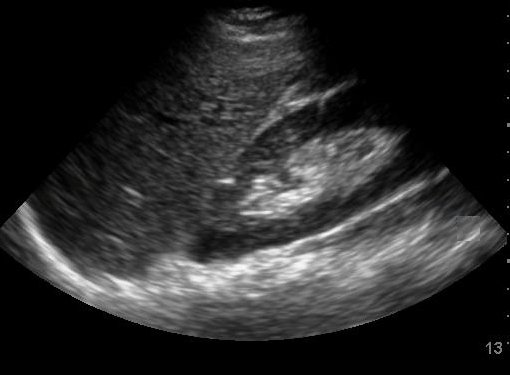

FAST Exam: Normal Morrison’s Pouch

Keywords: radiology, normal, renal, Morrison’s pouch, trauma, liver, ultrasound, FAST exam